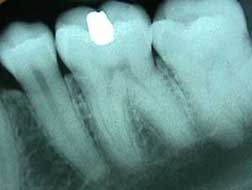

Woman in dentist's chair. D When you get an X-ray taken at a hospital, X-ray sensitive film is put on one side of your body, and X-rays are shot through you. At a dentist, the film is put inside your mouth, on one side of your teeth, and X-rays are shot through your jaw, just like in this picture. It doesn't hurt at all - you can't feel X-rays.

X-ray of a tooth D Because your bones and teeth are dense and absorb more X-rays then your skin does, silhouettes of your bones or teeth are left on the X-ray film while your skin appears transparent. Metal absorbs even more X-rays - can you see the filling in the image of the tooth?